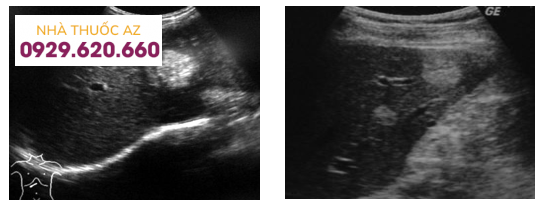

1.1 Siêu âm gan thông thường

Do tính sẵn có rộng rãi, không có nguy cơ nhiễm xạ, siêu âm thường là bước chẩn đoán đầu tiên đối với các u máu trong gan. Hạn chế chính của siêu âm gan là sẽ phụ thuộc vào người thực hiện và bệnh nhân.

Trên siêu âm thông thường, xuất hiện như một nốt đồng âm giảm phản âm, với bờ rõ ràng và tăng cường âm thanh phía sau. Hơn nữa, trong các lần kiểm tra tiếp theo hoặc trong khi so sánh hình chụp hiện tại với những lần trước, u máu trong gan thường không thay đổi về kích thước.

Bên cạnh đó, siêu âm gan còn có độ chính xác tốt trong việc phân biệt với các khối tăng phản xạ ác tính (độ nhạy 94,1% và độ đặc hiệu 80,0% đối với tổn thương đường kính dưới 3 cm). Sự vắng mặt của dòng máu tổn thương trong u máu trong gan trên siêu âm gan cũng là một dấu hiệu đáng tin cậy để chẩn đoán phân biệt với ung thư biểu mô tế bào gan, thường có mạch máu bên trong hoặc phúc mạc.

Một chẩn đoán phân biệt khác cần được xem xét trên siêu âm gan là tăng sản nốt khu trú, có đặc điểm là “dấu hiệu hình bánh xe”. Ngoài ra, cần thận trọng khi đánh giá gan nhiễm mỡ, trong đó u máu điển hình có thể giảm âm so với nhu mô gan giảm âm mạnh.

Siêu âm gan thông thường giúp phát hiện u máu trong gan